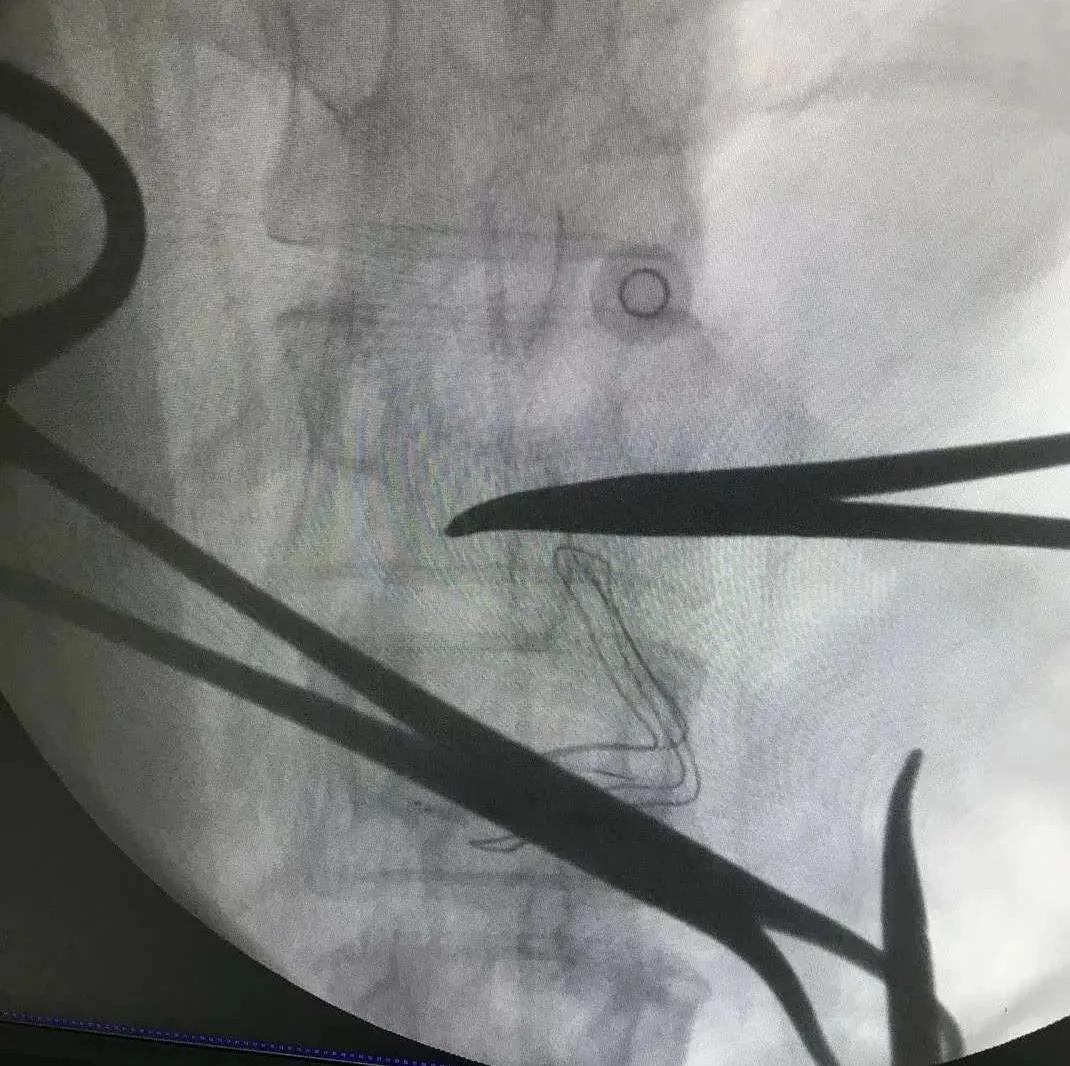

几经周折,尹女士来到了河南省肿瘤医院疼痛科,与科室副主任谢广伦充分沟通后,制定了“行鞘内镇痛”手术方案。经过手术治疗后,尹女士的疼痛得到了极大的缓解。

鞘内镇痛治疗是将导管置入蛛网膜下腔,并将给药装置植入到患者腹部皮下,通过体外连接智能化镇痛泵让*啡吗**等止痛药“一路畅通”的抵达“目的地”中枢神经系统,从而安全有效地为顽固性疼痛患者进行镇痛的一种方法。

鞘内镇痛手术创伤小,用药量仅为静脉用药的一小部分,大大降低了药物的副作用,而且可以根据病人疼痛的程度调节给药剂量。